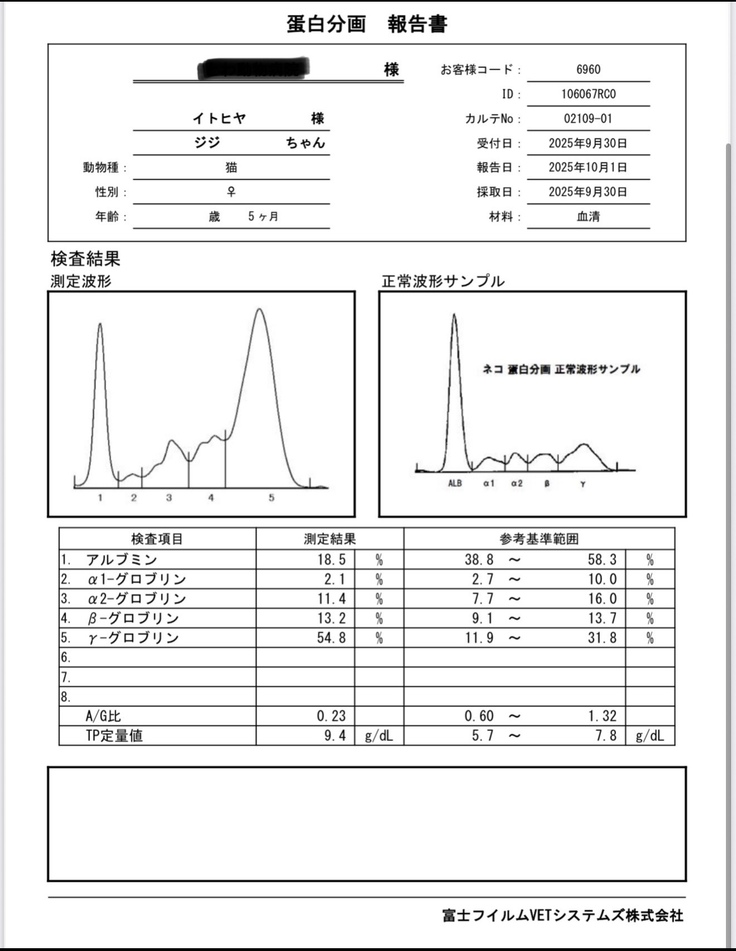

⬇️エコーの写真です。

黒い部分が腹水だそうで、黒い部分が見えてはいけないと説明を受けました。

すぐに血液検査など詳しい検査をしていただき、出た結果です。

タンパク質からの計算式に基づいて、この時点でおそらくFIPで間違いないだろうとの診断でした。